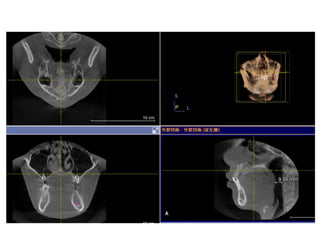

RME

• Maxillary constriction in particular has been

postulated to play a role in the pathophysiology

of OSA because of its association with low tongue

posture that may contribute to the orophayrnx

airway narrowing (Subtelny 1954).

• Pirelli et al. grouped 31 children with OSA and

followed them up to 4 months after RME

treatment. All of these children had their apnea-

hypoapnea index decreased while their mean

maxillary cross sectional width expanded to

about 4.5mm.

790516

810410

蕭郁庭